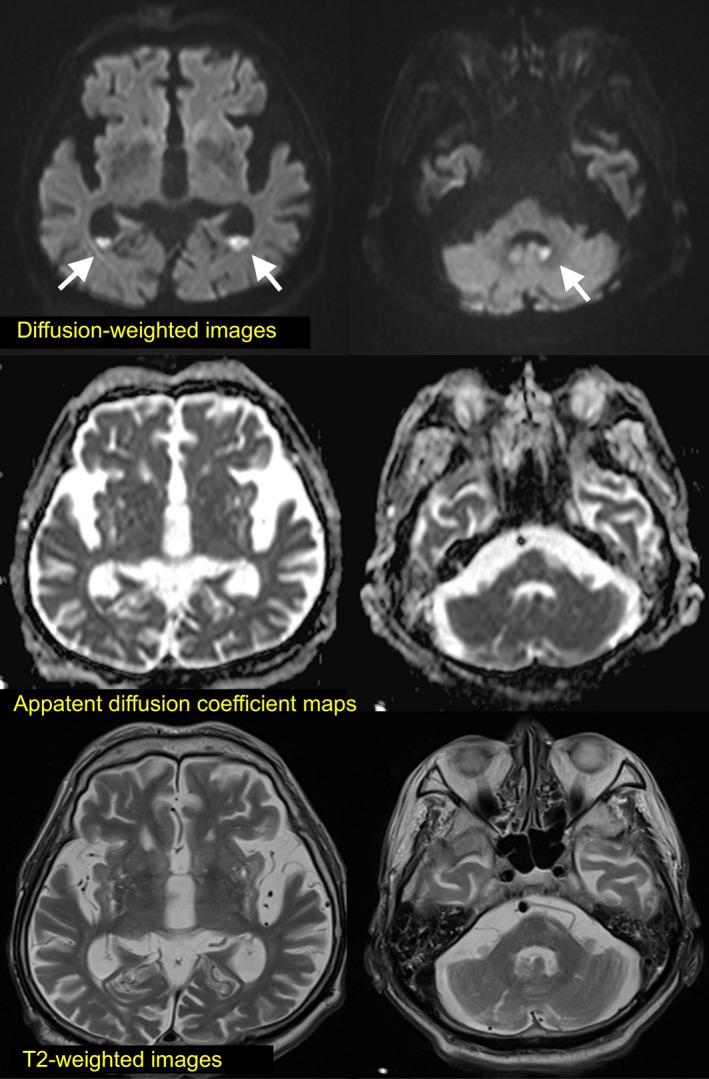

Invasive infection due to subspecies causing endocarditis and ventriculitis: A case report.

We aim to raise awareness of the role of subsp. (SDSE) in causing endovascular and central nervous system infections, and to promote recognition of SDSE as a pathogen that may cause serious invasive infections.